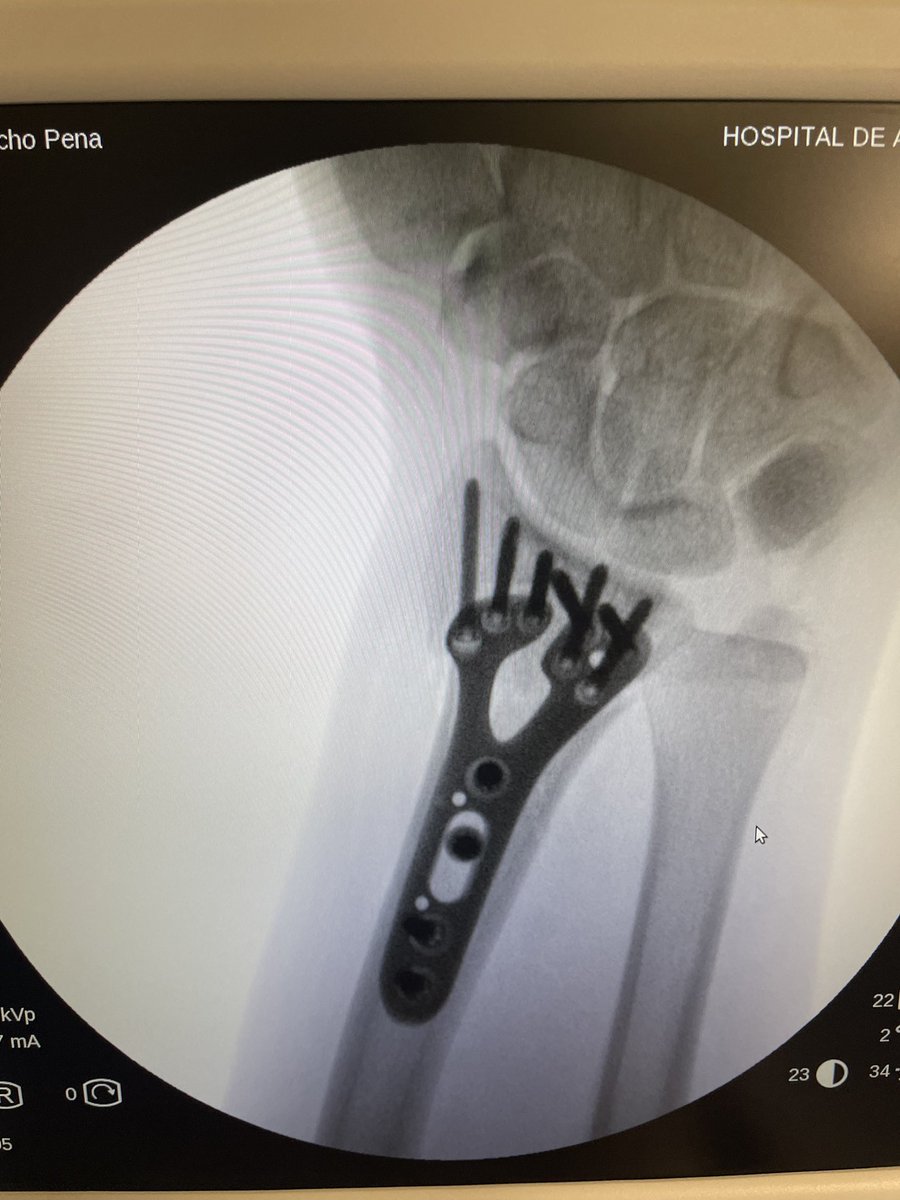

Always check neurovascular status after distal radius fracture. Here we can see an open fracture and ulnar affection. It is important to check before and after reduction, neurovascular problems. An ulnar nerve injury grade II-III axonotmesis. Always fix and check